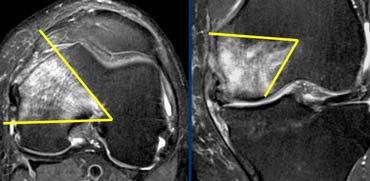

Hội chứng ma sát dải chậu chày

Vị trí ma sát bất thường thường gặp là giữa dải chậu chày và lồi cầu ngoài, hay xảy ra ở vận động viên đi bộ tốc độ cao, đạp xe và đôi khi ở người chạy bộ.

Khi túi hoạt dịch hình thành tại vị trí này, tình trạng này được gọi là ‘Hội chứng ma sát dải chậu chày’.

Hình bên trái là một vận động viên đi bộ tốc độ cao với triệu chứng đau mặt ngoài gối.

Bình thường phải có mô mỡ giữa dải chậu chày và lồi cầu ngoài, nhưng trong trường hợp này mô mỡ không còn hiện diện.

Hội chứng ma sát dải chậu chày: Dịch trong túi hoạt dịch thấy được giữa dải chậu chày và xương đùi (mũi tên vàng). Dịch khớp dừng lại tại các mũi tên đỏ.

Cùng bệnh nhân trên. Trên các lát cắt axial, có thể thấy dịch trong túi hoạt dịch nằm giữa dải chậu chày và xương đùi bên dưới.

Đôi khi cần phân biệt dịch tại vị trí này với dịch khớp.

Cần xem xét toàn bộ các lát cắt hình ảnh.

Trong trường hợp này, dịch khớp dừng lại tại các mũi tên đỏ.